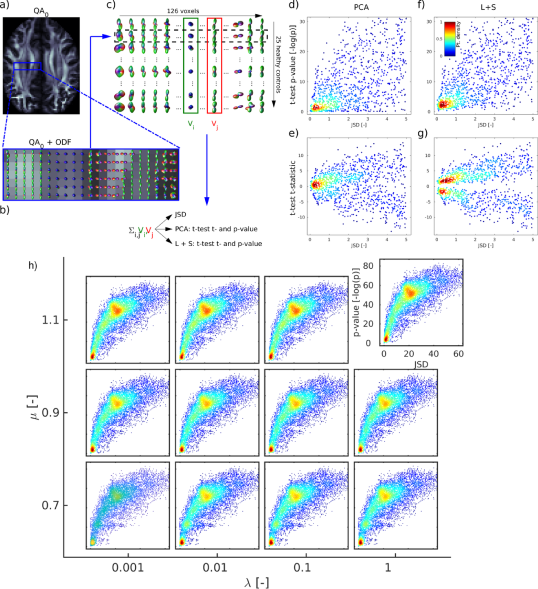

The relationship between in vivo group differences and t-test statistics and p-values is explored in Figure 6. A central segment is randomly taken from the registered in vivo whole brain HCP dataset (Fig. 6a,b). Group differences are artificially introduced by comparing all ODFs of each pair of voxels in the segment (Fig. 6bc). The results of these comparisons using (Fig. 6de) and (Fig. 6fg) are plotted versus the JSD of the average ODFs of the respective voxels. The detected p-values are smaller (larger values) when analyzing over , indicating higher detected significance. The comparison test is in addition inconclusive (p close to 1) on less occasions. These beneficial properties of the analysis of remain for a wide range of values for -matrix decomposition parameters and (Fig. 6h).